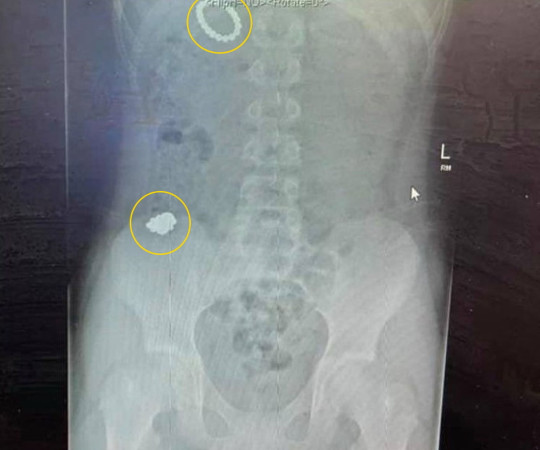

Rhiley a fost supus unei radiografii și surpriză! Medicii au informat-o pe mama acestuia că băiatul a înghițit 54 de bile magnetice. Ulterior, copilul a fost supus unei intervenții chirurgicale, care a durat șase ore.